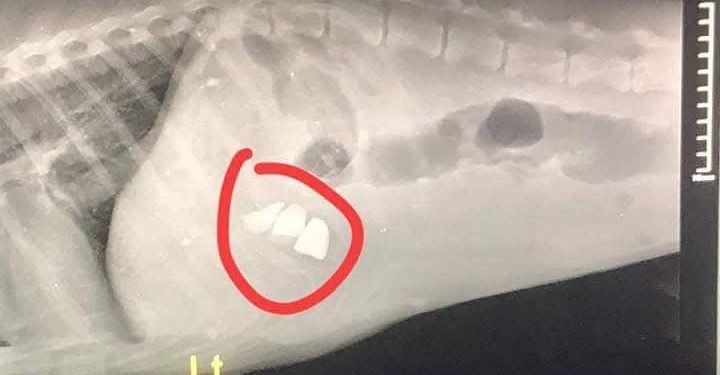

ამ რენტგენის ფოტოთი გიპასუხებთ ყველას, ვისაც გგონიათ რომ ძაღლები აგრესიულები არიან.

ამ წერტილებს ხომ ხედავთ, ეს არის ქვები, რომელიც მშიერმა ძაღლმა შეჭამა, იმიტომ რომ შიოდა და სხვა გზა არ ქონდა. აი ასეთი ტანჯვის გადატანა უწევთ ქუჩაში ძაღლებს და თქვენს მოქნეულ წიხლს თუ იგერიებენ, ნუ გიკვირთ. თქვენი ცხოვრების 1 დღე რომ გაატაროთ, ქუჩის ძაღლის ცხოვრებით, ისე რომ გშიოდეთ ქვებს ჭამდეთ, დარწმუნებული ვარ უარესს გააკეთებდით.

ეცადეთ აგრესიის მაგივრად 1 ლუკმა მიაწოდოთ და დამიჯერეთ, არცერთი ძაღლი არ დაგგლიჯავთ!